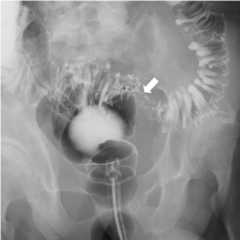

Overhead image from a small bowel

a: Overhead image from a small bowel follow-through in a patient with a history of Crohn’s disease demonstrates evidence of terminal ileal wall thickening, causing narrowing of the lumen

b: Spot view of the terminal ileum in a small bowel follow-through demonstrates similar findings in a second patient with terminal ileitis

Image: “Barium upper GI series showing a stricture (arrow) in the transition of the second to the third portion of the duodenum” by Patel P. License:CC BY 4.0